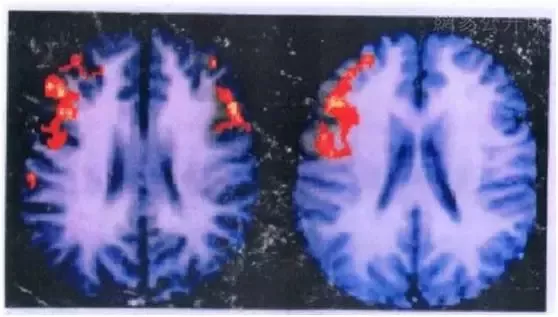

著名教授洪兰,专门研究了男女在说话时,他们的大脑活动区域有何差别。

图左:女生——女生说话时,大脑两边都有活跃区域,说明同时动用了左右脑。

图右:男生_主要是左边的大脑会亮起来,男生面对矛盾时,主要用左脑。

因为右边大脑负责情绪,左边大脑负责语言。所以女生说话时,是带着情绪的,是在表达自己的情感;而男生说时,情绪很少,主要是传递信息。